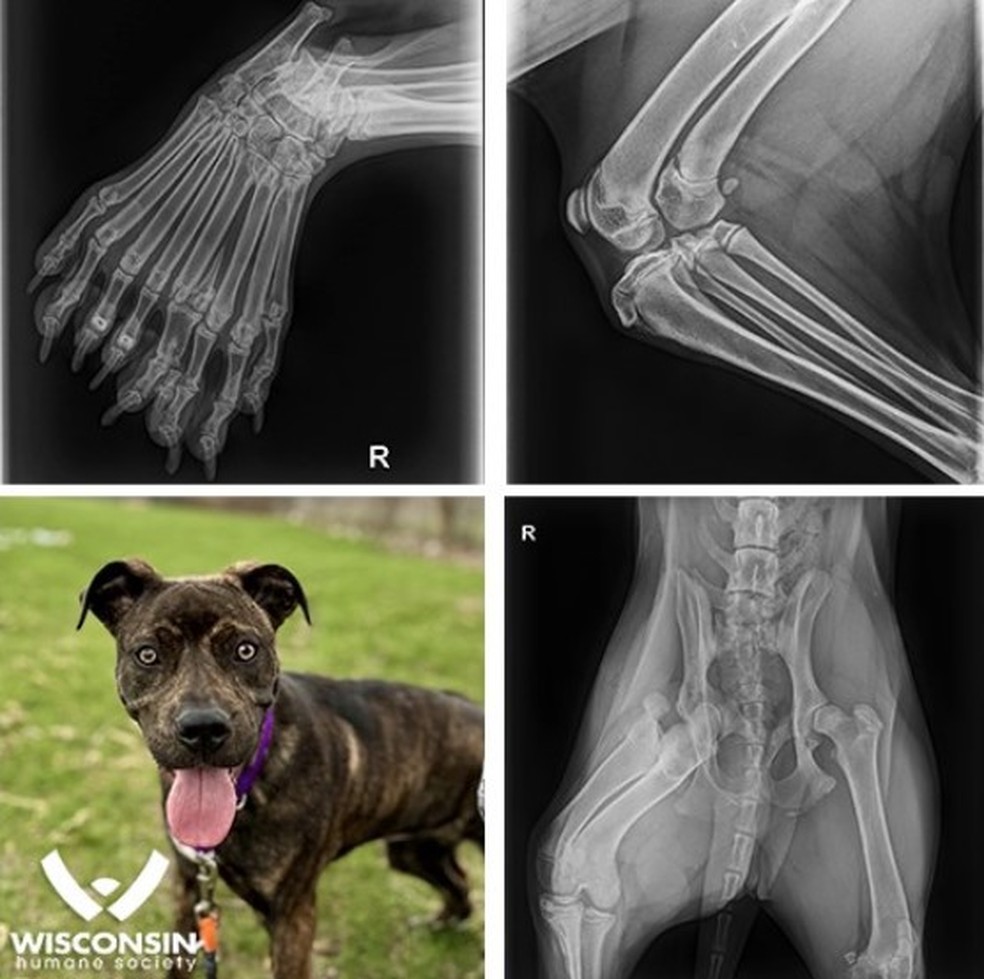

A perna traseira direita de Bella era incomumente larga, tinha dedos extras e parecia não ter a estrutura canina padrão. Com apenas seis meses de idade, Bella sofre de um raro defeito congênito conhecido como dimelia, que significa duplicação de certos ossos.

Radiografias mostraram um fêmur extra, duas tíbias, duas fíbulas e nove dedos na pata traseira – muito mais do que os quatro ou cinco habituais. Isso faz de Bella uma raridade no mundo da medicina veterinária.

A raridade é tanta que Bella tem sido descrita como um "unicórnio canino"."É o primeiro caso de dimelia que vimos na história da nossa organização e, até onde sabemos, é um dos poucos casos documentados de dimelia em um cão", declarou a Humane Society na sua página no Facebook.O sucesso na rede social não tardou para Bella.